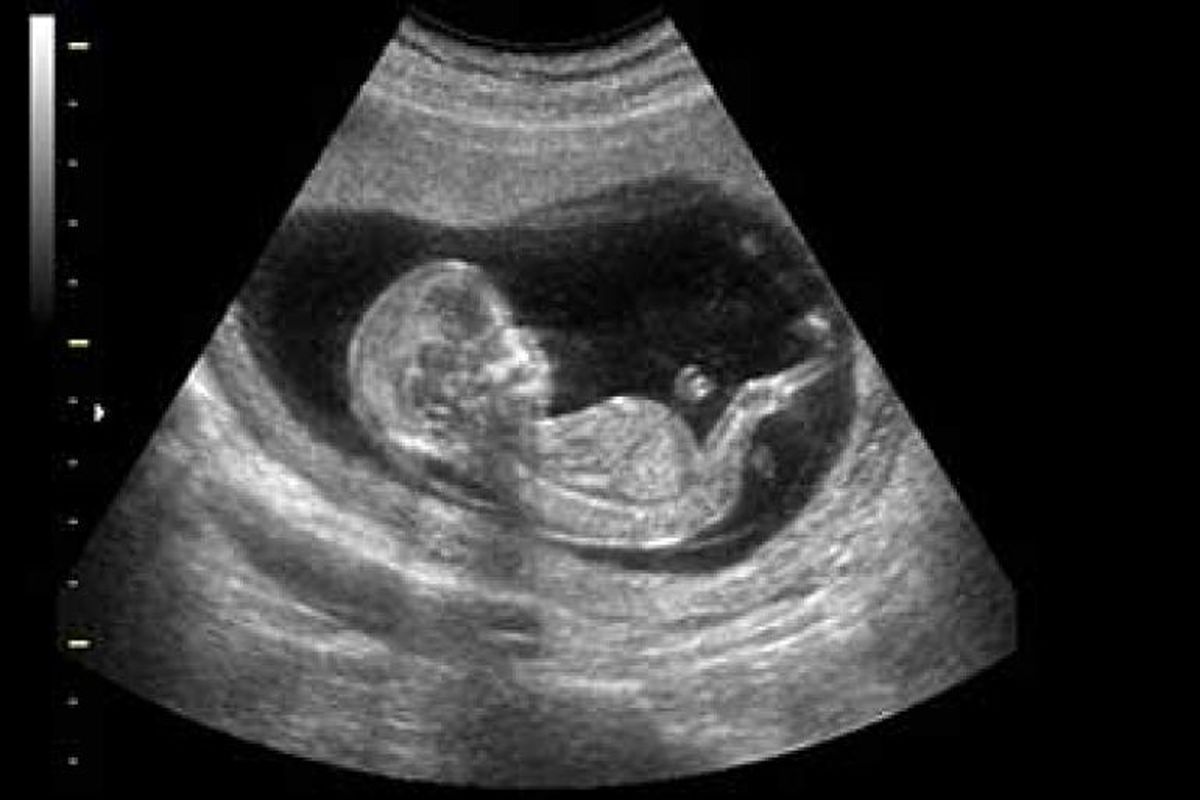

به گزارش خبرگزاری موج، برای پاسخ دادن به پرسش‌هایی از قبیل سلامت جنین در شکم مادر ، پزشکان نخستین سونوگرافی از جنین را در زنان باردار بین هفته‌های ۹ام تا ۱۲ام انجام داده که از طریق آن می‌توان موارد زیادی را در مورد وضعیت سلامتی جنین تشخیص داد. با سونوگرافی حتی امکان تشخیص جنسیت جنین پس از گذشت چند ماه وجود دارد.

در هنگام سونوگرافی یا به عبارتی در اثر سونوگرافی، بیمار نه دردی احساس می‌کند و نه اشعه‌ای دریافت می‌کند و امواج صوتی برخلاف پرتونگاری، تأثیر منفی روی جنین و سلول‌های آن ندارند. پزشک با کمک این امواج می‌تواند اندام‌های گوناگونی را معاینه کند. امواج صوتی تصاویری از بافت‌ها و ارگان‌های داخلی بدن انسان می‌دهند که پس از پردازش بر روی مانیتور قابل مشاهده است.

این سونوگرافی‌ها معمولا برای بررسی ضربان قلب، تخمین مدت بارداری، موقعیت جنین و ناهنجاری‌های احتمالی به کار گرفته می‌شود. با این حال بسیاری از پزشکان نسبت به انجام سونوگرافی‌های غیرضروری، تعدد آنها و صدمه‌ای که این معاینه‌ها می‌توانند در ماه‌های مشخصی از بارداری روی جنین بگذارند، هشدار می‌دهند.

درحالی که پزشک در حال سونوگرافی است، والدین هم این امکان را دارند که حرکات جنین را روی صفحه‌ی نمایش کوچکی دنبال کنند.